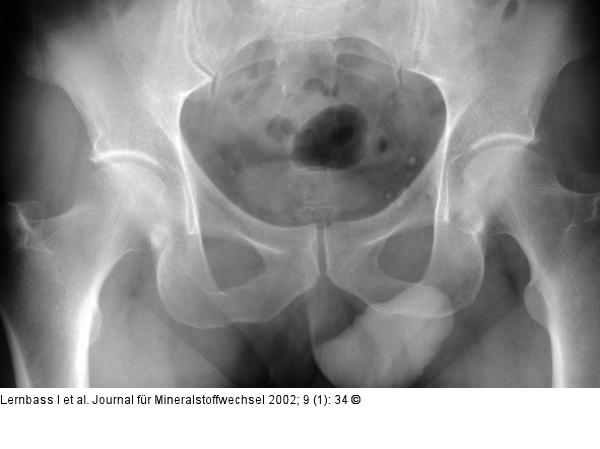

Abbildung 3: Osteoporose - Becken Beckenübersichtsaufnahme mit altersentsprechendem Befund. Trabekuläre Binnenstrukturen im proximalen Femur entsprechen einem Singh-Index IV. |

Beckenübersichtsaufnahme mit altersentsprechendem Befund. Trabekuläre Binnenstrukturen im proximalen Femur entsprechen einem Singh-Index IV. |